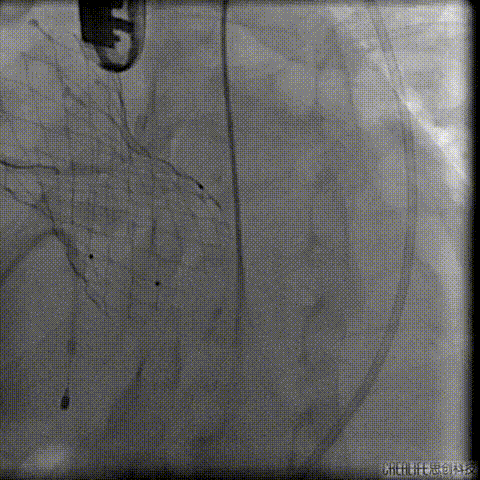

经瓣架网眼挂上指引管

反复确认指引管经瓣架网眼

指引管经瓣架网眼

经网眼置入导丝

置入4.0mm*23mm微创冠脉支架

定位并释放支架

退出球囊扩张突入瓣架部位